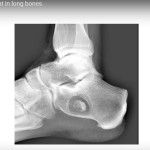

Evaluation of Skeletal Dyplasia

Courtesy: Mary Wyers MD Address: 225 E Chicago Ave, Chicago, IL 60611, USA